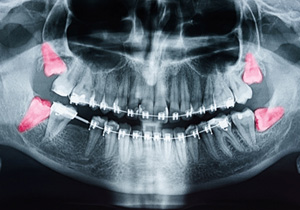

In most cases, wisdom teeth simply don’t have enough room to emerge properly because of the surrounding teeth, and this leads to potentially serious problems. They may erupt at a sideways angle, only partially push through the gum line, or even become trapped altogether. These instances lead to higher risks of infection, facial swelling, and other unpleasant consequences. Fortunately, our doctors can inspect wisdom teeth with the help of digital X-rays before they’ve fully erupted. If any of these problems seem likely, we may recommend extraction as a preventive measure.